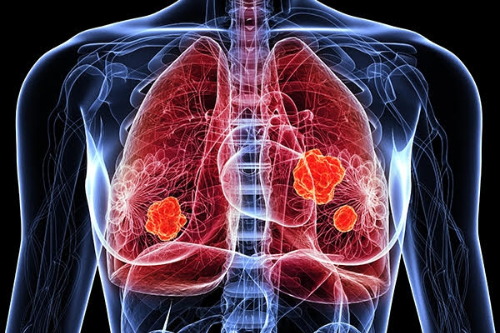

폐암이란

폐암이란 우리 몸의 폐에 생긴 악성 종양을 말합니다. 원발상 폐암이라고 해서 폐 자체에서 발생하거나 다른 장기에서 생긴 암이 폐로 전이될 수도 있습니다. 원발성 폐암의 종류에는 암세포의 형태와 크기에 따라 비소세포 폐암과 소세포 폐암으로 구분합니다. 폐암의 80~85%는 비소세포폐암에 해당하며 이것은 다시 선암(샘암), 대세포암, 편평상피세포암 등으로 나뉩니다. 그리고 소세포폐암은 대체로 악성도가 높아 발견되었을 때 이미 림프관 또는 혈관을 통하여 다른 장기나 반대편 폐, 종격동, 기관, 식도, 대동맥, 양쪽 폐 사이의 공간으로 심장 등으로 전이되어 있는 경우가 많습니다.